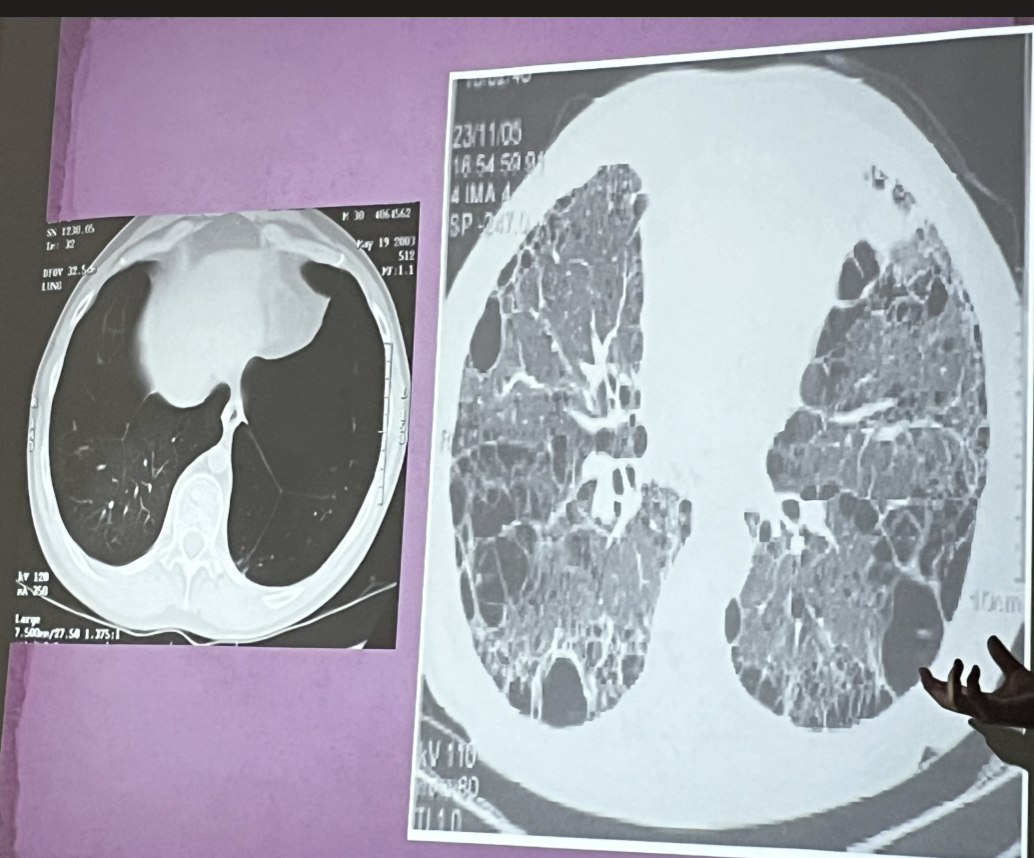

Rx: Patrón bronquial

A

• Aumento de la trama vascular

• Patrón de riel

• Hiperinsuflación